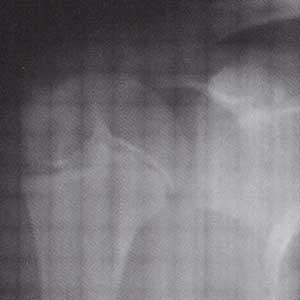

正常の肩関節 右と左 骨頭のところに線が入って見えるのも正常→骨端線 コッタンセン

痛んでいる肩関節(写真左側)→リトルリーガーズショルダー

投球側の骨頭 コットウ がずれています。 (写真右側は非投球側)